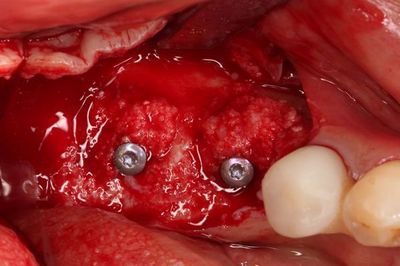

ドリリングを進め、軟組織を除去しました。

骨欠損部分には骨補填材を填入しますが、まずは埋入を行います。

無事に2本のインプラントの埋入を終えました。

トランスファージグを取り外しました。

ヒーリングスクリューH0.5mmでスクリューホールを保護します。

ここで、ドリリング時の骨切削片をボーンコレクターで回収したものを用います。

骨欠損部分に自家骨切削片を置きました。

わずかにハイドロキシアパタイトを混ぜて、吸収防止対策をしています。